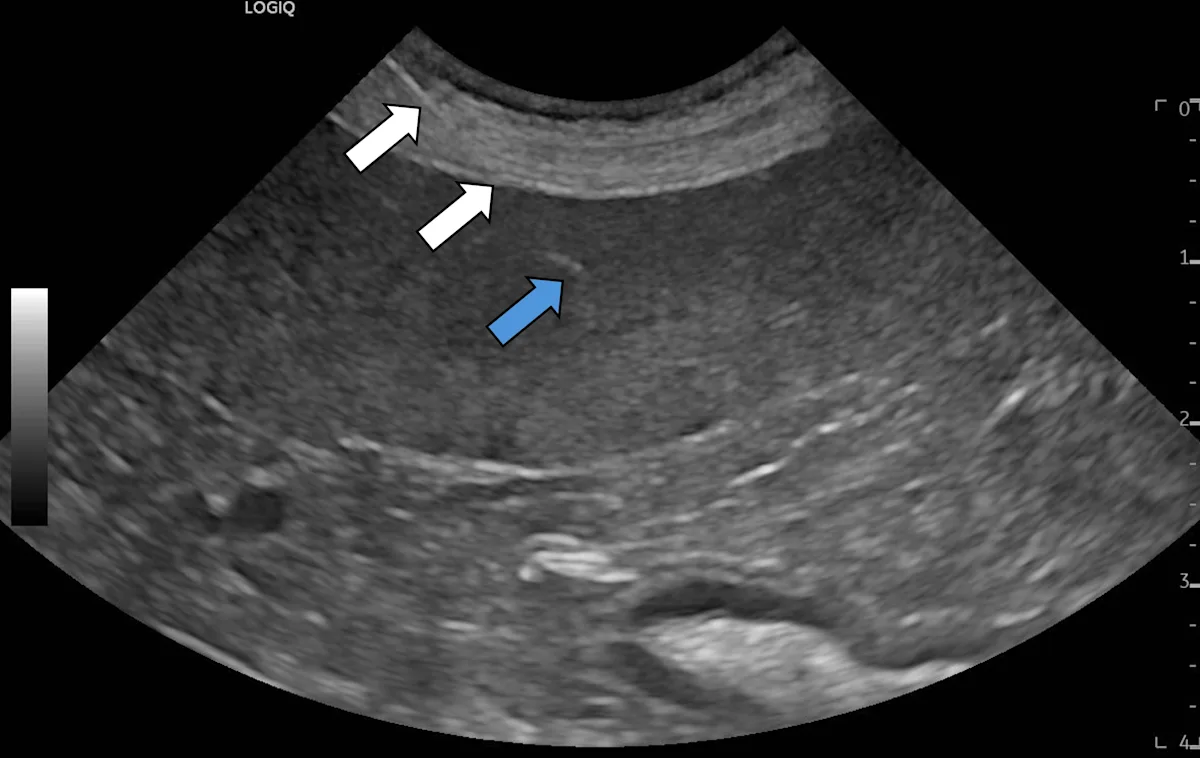

Step 7: Insert the Needle & Collect a Sample From the Target Lesion or Organ

Ensuring the needle is in the same plane as the beam of sound, insert the needle through the skin immediately next to the transducer and a short distance into the superficial soft tissues. Identify the needle on the ultrasound machine screen as a thin, hyperechoic linear structure. Make small adjustments to the needle or transducer so the entire needle (white arrows), including the tip (blue arrow), is completely visible.

Adjust the needle angle so the intended path is directed at the target, and advance the needle. Once inside the target, advance and withdraw the needle 4 to 5 times within the target if performing FNNA or apply suction (2-3 mL) 1 to 3 times if performing FNA. Do not advance/withdraw or reposition the needle while the patient is moving, including when the patient is taking large breaths, as this can cause the abdominal viscera (especially the liver) to move caudally. Remove the needle from the patient once sampling is complete.